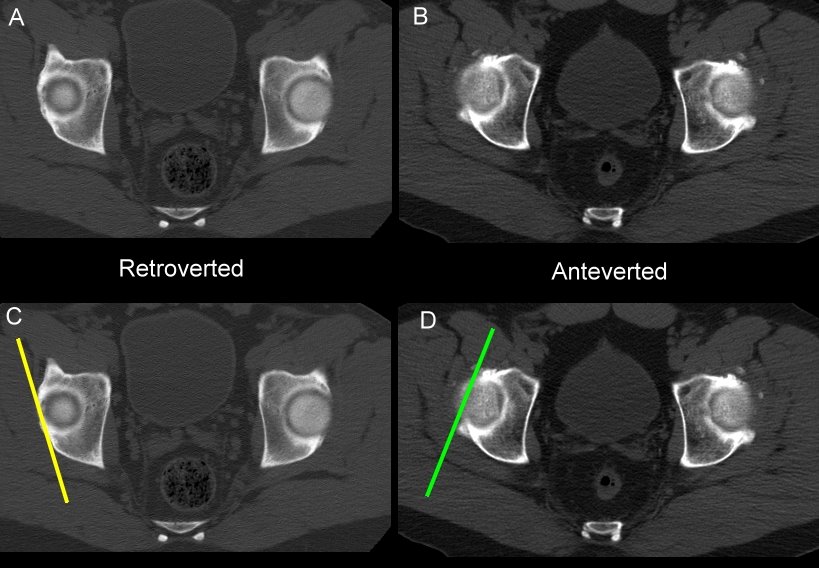

← Talking about hip retroversion